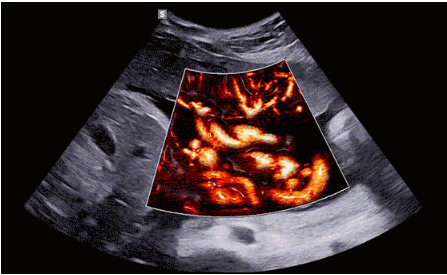

CrystalLive?是三星最新的超聲成像引擎,同時增強了2D圖像處理能力、3D渲染能力和彩色信號處理能力,能夠在復雜情況下提供出色的圖像性能,具備檢測外周血管、微循環(huán)血流的能力。

2D成像方面,Hera i10集成了包括ShadowHDR?、HQ-Vision?、ClearVision等多項具有三星“血統(tǒng)”的技術,加強了圖像的陰影抑制、減少偽影、緩和模糊區(qū)。